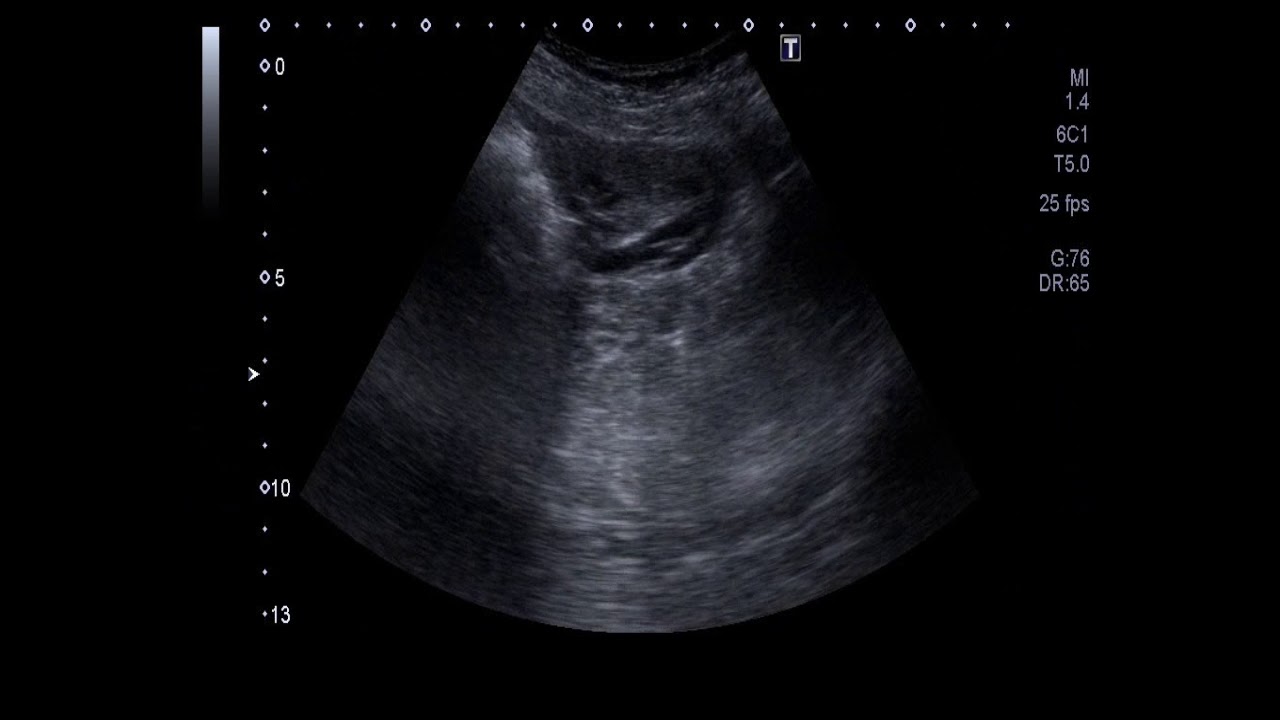

8) Large cystic adnexal mass - Highly septated, thick walled mass. Differential can be an abscess like in TB, if history of fever supports it.